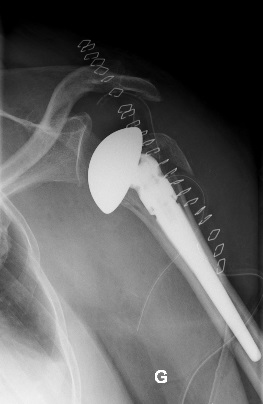

Dans ce propos, nous allons tâcher d’éclairer le lecteur sur la nature des implants utilisés en chirurgie orthopédique pour réaliser les prothèses articulaires (hanche, genou, épaule, coude, cheville, articulations des doigts…). Les termes prothèses articulaires et arthroplasties sont interchangeables même si une nuance puriste peut exister. Le but d’une prothèse articulaire est de remplacer une articulation détruite suite à l’usure liée à l’âge, une infection, une tumeur ou un traumatisme par des implants inertes destinés à restaurer la fonction. On précisera cependant qu’il ne s’agit pas ici de prothèses – appareillages destinées à remplacer un membre amputé.

Actuellement, l’amélioration de la qualité des matériaux ainsi que de leur usinage, surtout le polissage de la surface de friction, ont permis de porter la durée de vie des prothèses au-delà de 30 ans. Trois catégories de matériaux sont actuellement utilisées. Il s’agit des alliages métalliques, des céramiques et du polyéthylène de haute densité. Des essais d’implants en carbone sont en cours.

Les alliages métalliques sont essentiellement en chrome – cobalt et en titane. Les céramiques sont des matériaux non métalliques et non organiques obtenus par l’effet de fortes températures sur de l’alumine ou du zircon. Le polyéthylène est un matériau plastique issu de l’industrie pétrochimique. Il sert à constituer la surface de friction des implants. L’introduction du ciment acrylique dans la fixation des implants à l’os date du début des années 60. Depuis le milieu des années 80, le concept de prothèse sans ciment est apparu. Le principe consiste à recouvrir la surface de contact des implants avec l’os d’un revêtement dit ostéo-conducteur. Il s’agit de l’hydroxyapatite, un composant minéral naturel de l’os que l’on produit artificiellement. Au contact de la prothèse, l’os du voisinage identifie cet hydroxyapatite comme un de ses propres constituants et le colonise. La prothèse devient ainsi intégrée à l’os. On parle alors de stabilité secondaire. Naturellement, en attendant cette repousse d’os sur le revêtement d’hydroxyapatite, la stabilité primaire est assurée par l’impaction en force de la prothèse dans l’os et éventuellement fixée par des vis complémentaires. Les couples de friction (surface de frottement des implants) sont de plusieurs sortes : métal – PE, céramique – PE, céramique – céramique. Le couple métal – métal dit de gros diamètre a été utilisé au moins durant trois périodes depuis le 20ème siècle dont la dernière au-début des années 2000 avant d’être à nouveau abandonné pour cause de relargage excessif de particules de métal dans l’organisme.